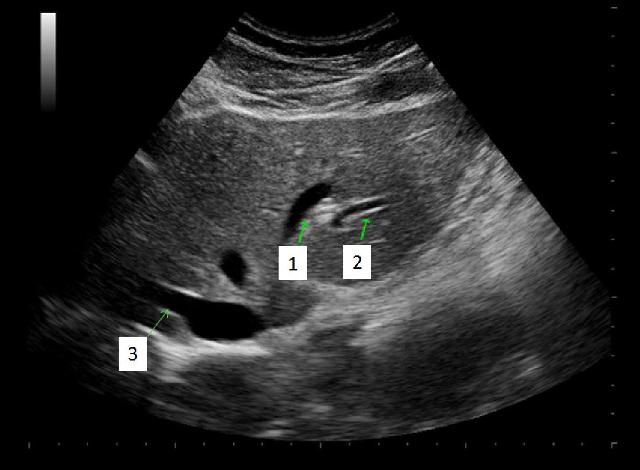

What structure/vessel is indicated by #3?

Gastroduodenal artery

What structure/vessel is indicated by #2?

Head of pancreas

What structure/vessel is indicated by #1?

Medial branch of LPV

Left portal vein

What structures/vessel is indicated by #5?

Tail of the pancreas

Which structure/vessel is indicated by #4?

Body of the pancreas

Lateral branch of LPV

Splenic vein